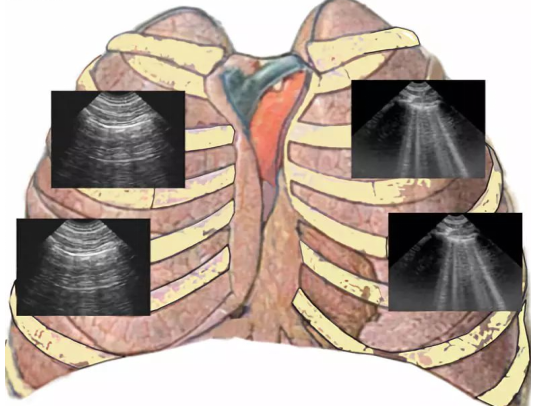

肺部超声有多种扫查方案,包括BLUE方案、BLUE-plus方案、十二分区法、八分区法、m-BLUE方案、pBLUE方案等。急性呼吸衰竭属于危重症,需要临床医生快速做出判断,快速筛查有无致命性疾病存在。2008年发表在Chest 杂志上的一篇文章[6],就BLUE方案对急性呼吸困难的超声鉴别给了我们很好的提示。这项研究指出:BLUE方案流程在3 min内通过对肺和深静脉血栓的快速筛查,可对90.5%的急性呼吸衰竭或低氧血症的病因做出快速、准确的诊断。另有学者于2019年在Am J Emerg Med 杂志发表文章[7],也对BLUE方案的准确性进行了评价,结果提示:BLUE方案对心源性肺水肿、肺炎、气胸以及肺栓塞的诊断敏感性和特异性均较高。BLUE方案的实施要点包括探头选择、操作手法、动作要领以及检查点定位【具体不赘述】(图2)

图片

图2  BLUE方案实施要点